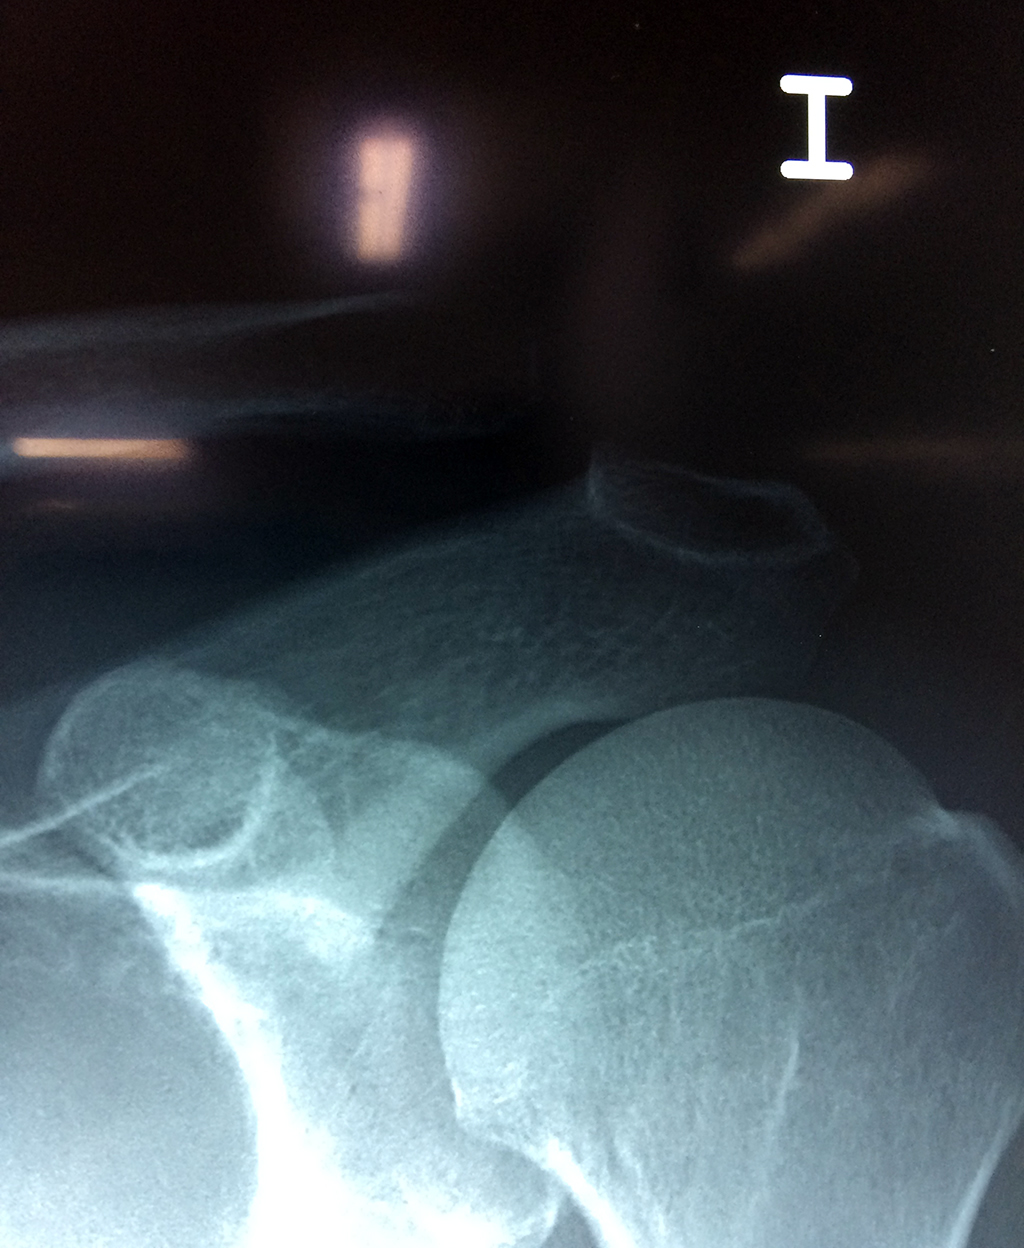

Cirugías de Hombros - Clavícula

La clavícula es un hueso largo, con forma de "S" itálica, situado en la parte anterosuperior del tórax. Junto con la escápula forman la cintura escapular. Se puede palpar por toda su longitud y se extiende del esternón al acromion de la escápula, siguiendo una dirección oblicua lateral y posterior.